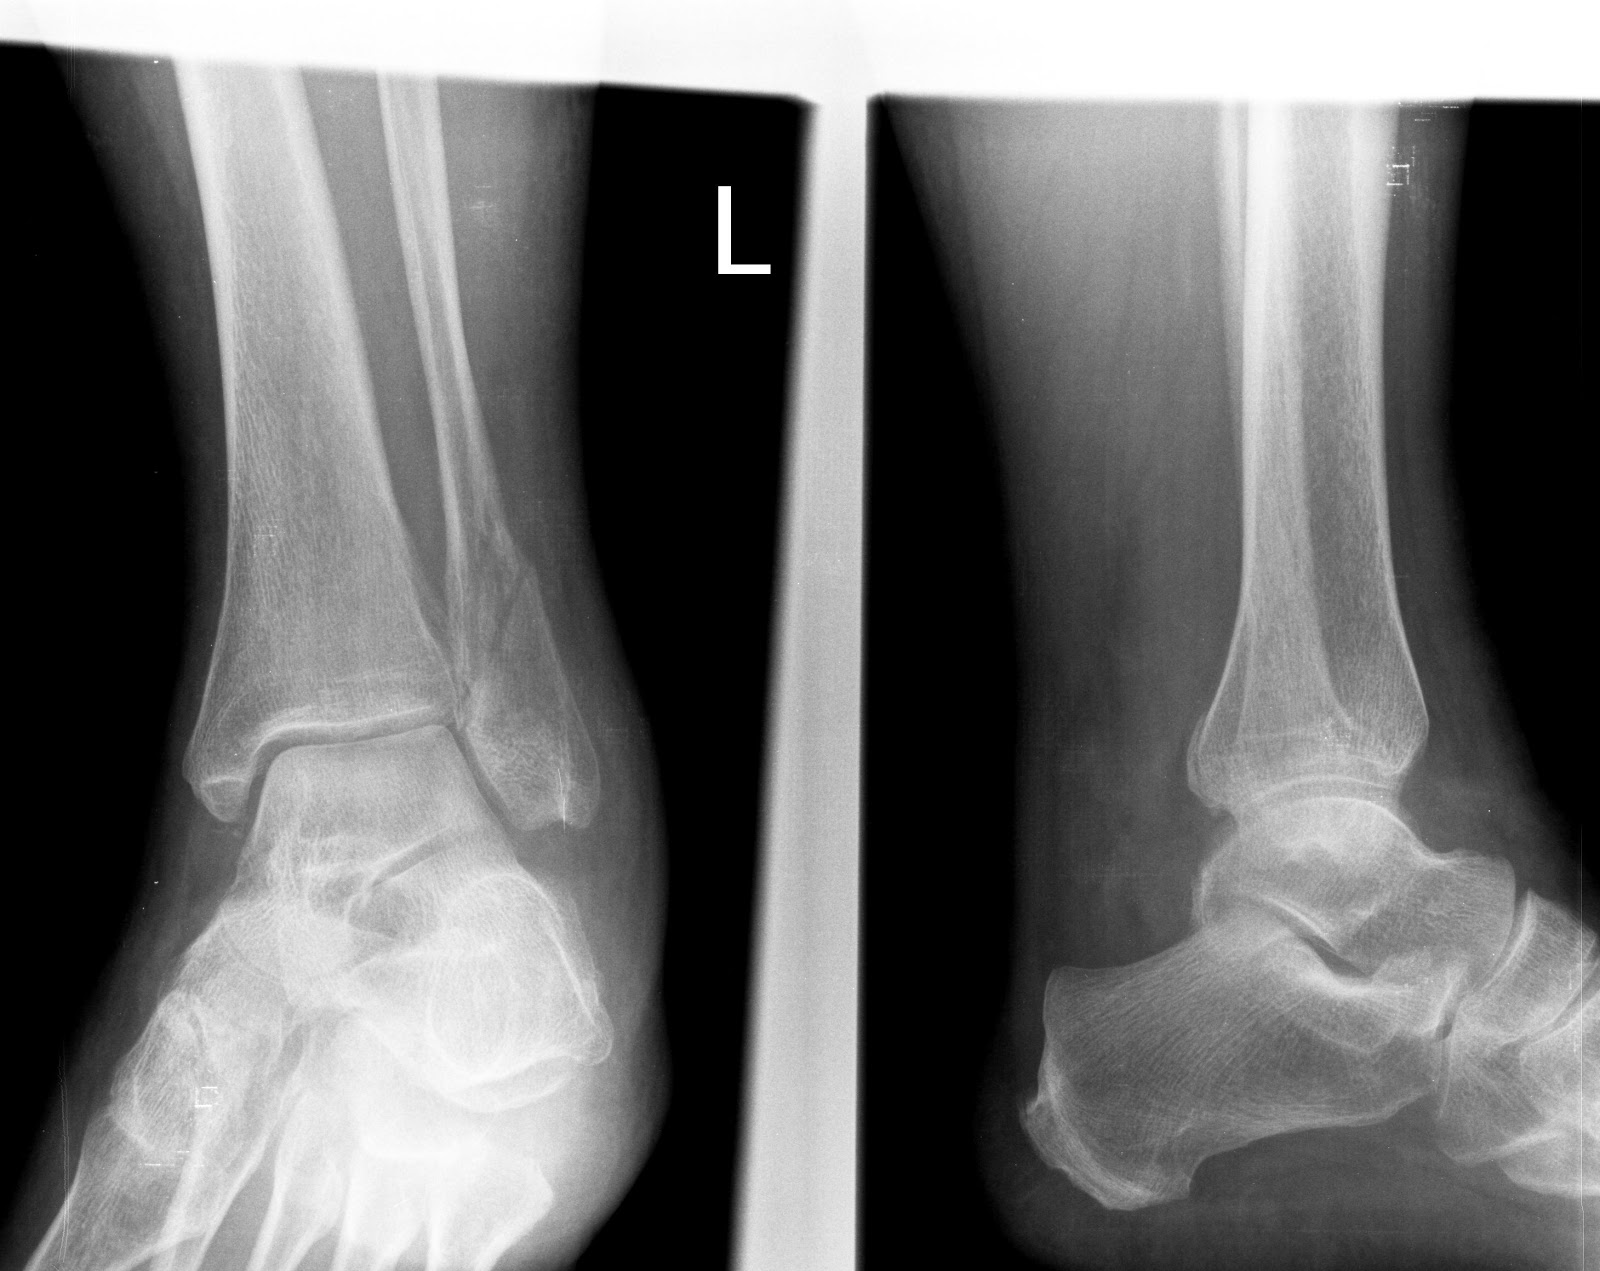

Weber C – Lauge-Hansen PE IV st. |

- Lauge-Hansen